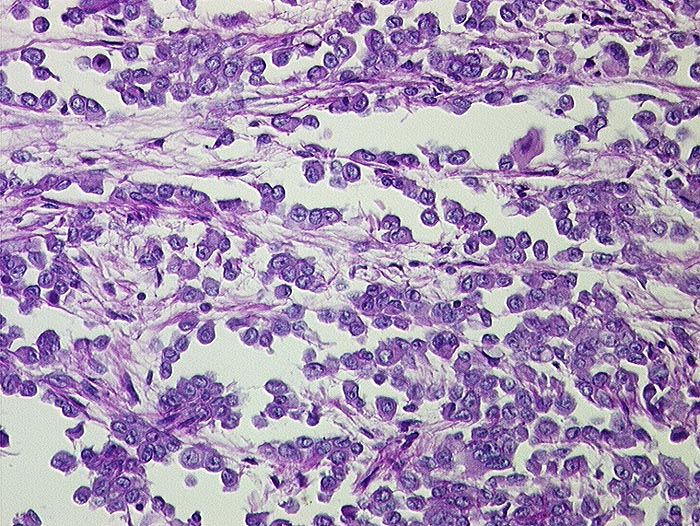

PathoPic ID 1540 - Malignes Mesotheliom epithelialer Typ

Malignes Mesotheliom epithelialer Typ

Kubische Zellen kleiden tubuläre Räume aus. Die Tumorzellen haben vesikuläre Kerne mit prominenten Nukleolen.

500ml seröser Ascites. Kleine Metastasen in der Lunge.